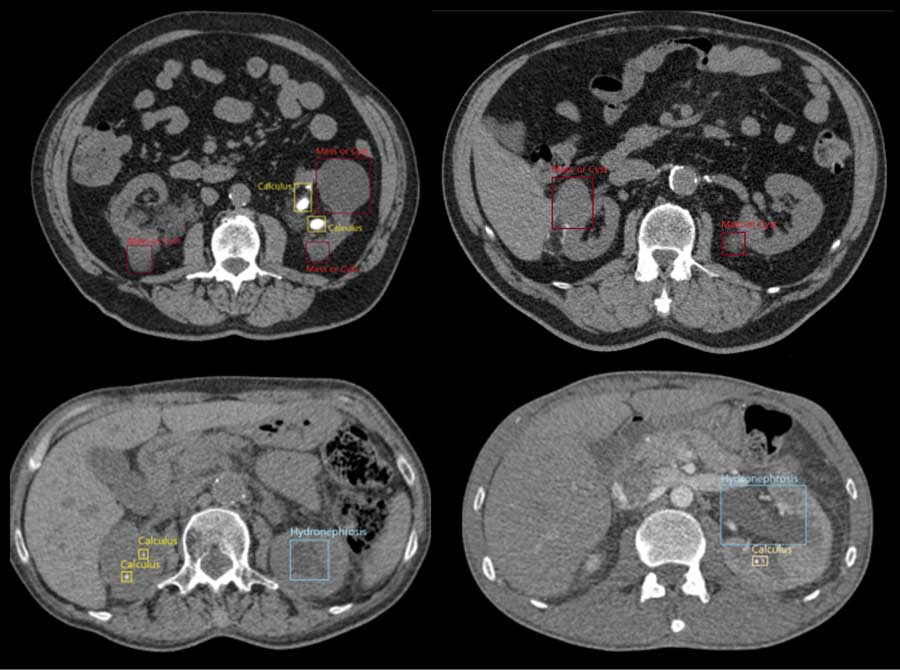

図:AIによる複数異常の検出例

世の中の多くのAI診断支援製品は、重篤な疾患の見逃し防止に焦点を置き、1つの疾患の診断を行います。一方MaestroAI®は、1つの臓器において正常とは異なる状態にある箇所(異常所見)を網羅的に検出することできます。これにより、より広範囲に医師の診断を支援し、医師不足解消を目指すソリューションです。